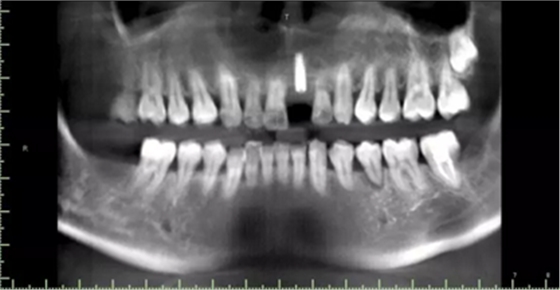

現(xiàn)病史:患者牙周病五年余,牙石(+++)、牙周病;15、26牙齲齒;,今就診我院,要求21牙種植修復(fù)。

1.術(shù)前CT

2.術(shù)前植體設(shè)計(jì)

術(shù)后CT